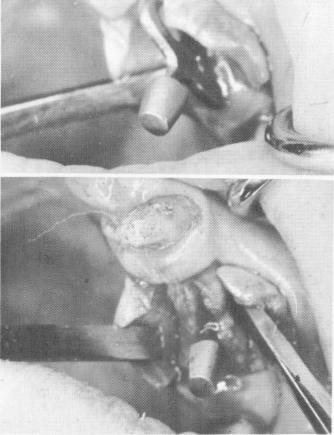

Only four of this patient's teeth remained: two maxillary cuspids and two molars. For additional support of a full arch restoration, a blade was diagnosed to be placed between the left cuspid and second molar (Fig. 11-68). The tissue was incised and

Fig. 11-69. The implant being seated in its site. (From Linkow, L. I.: The blade vent, a new dimension in endosseous implantology, Dent. Concepts 11:3-18, 1968.)